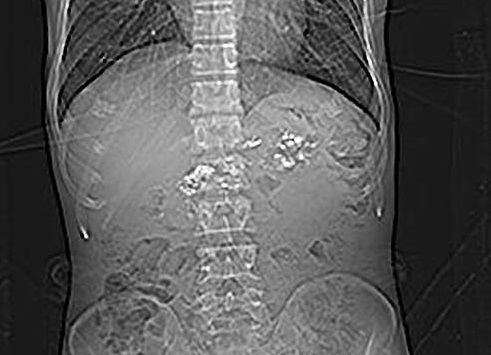

Image radiologique de

calcification du pancreas d'une pancreatite

chronique diagnostique par harzad sur un cliche de

face ASP a douleur de l'abdomen |